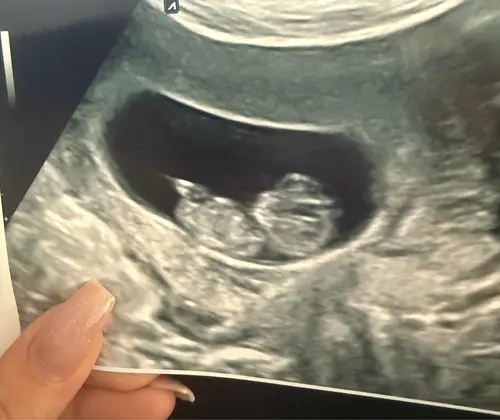

Met 10 weken is de nubtheorie inderdaad nog niet betrouwbaar. Ook ‘jongensnubs’ staan rond deze termijn meestal nog in de meisjes stand namelijk.

Ik denk bij jouw foto wel ook echt een jongen ik weet niet precies waarom haha , zouden jullie die van mij ook willen raden?

Haha ik vind het moeilijk om te zeggen, maar ik denk bij jou een jongetje. 😁

Dank je wel voor je gok, ik denk zelf ook dat het een jongentje is, en dank je wel voor je compliment is weer is iets anders haha